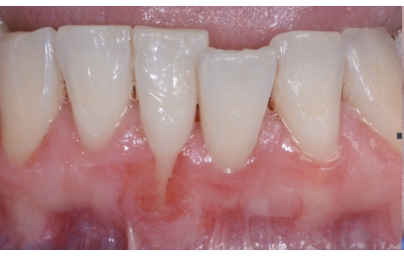

Q

what is this

A

necrotising periodontitis